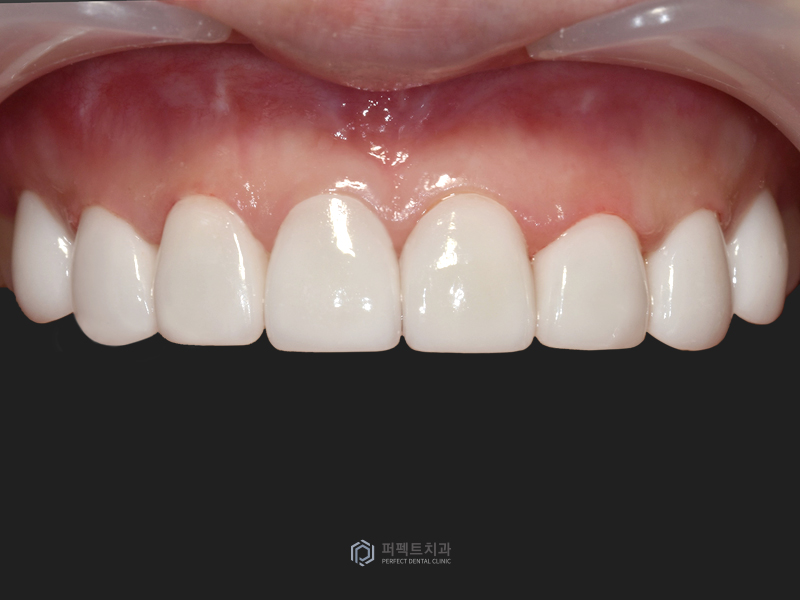

치아 색상은 환자 분께서 고르신 색상으로 만들어드렸고, 말씀드린 것처럼 앞니 두 개는 올세라믹 크라운, 나머지 치아는 폴리네이트로 치료를 하였습니다.

전후 사진을 비교해서 보시면 환자 분의 요구사항 대로 기존 치아보다 하얗고 밝게 만들어드렸습니다.

오늘 보신 케이스처럼 예전에 치료 받았던 보철물을 교체하기 위해 내원하시는 분들이 많이 계십니다. 예전에 했던 보철물들은 시간이 지나면서 교체가 필요한 경우, 즉 충치나 보철물에 문제가 생기는 이유들이 발생하는데 이번에 오셨던 환자 분은 앞니 두 개를 교체 하면서 치아를 밝고 가지런하게 개선하고싶어 하셨습니다.

그렇기 때문에 2개의 치아를 걷어내고 8개로 확장한 경우라고 생각하시면 될 것 같고, 나머지 치아는 거의 삭제를 안해서 환자분께서 만족하실 수 있는 치료가 되었습니다.